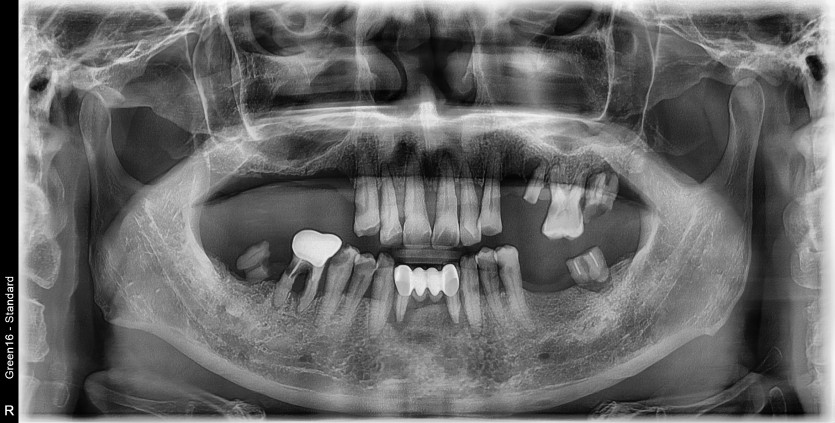

전체 임플란트 증례입니다.

17개의 임플란트로 완성하였습니다.